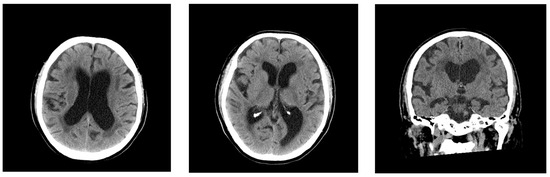

2.1. Case 1

2.2. Case 2